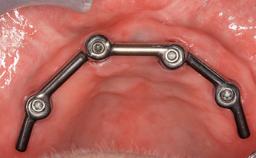

Fixed and removable prosthodontic implant therapy for restoration of the edentulous maxilla is both complex and challenging. Careful assessment and planning is needed in each individual case to explore whether a fixed or a removable solution will be the more suitable to satisfy the patient’s preference for optimal esthetics, phonetics, comfort and function. This Learning Pathway explores the prosthodontically driven treatment planning based on structured assessment, considered diagnosis and practical application in clinical case examples.

• recognize the importance of a prosthodontically driven plan and of planning implant configurations and placement accordingly